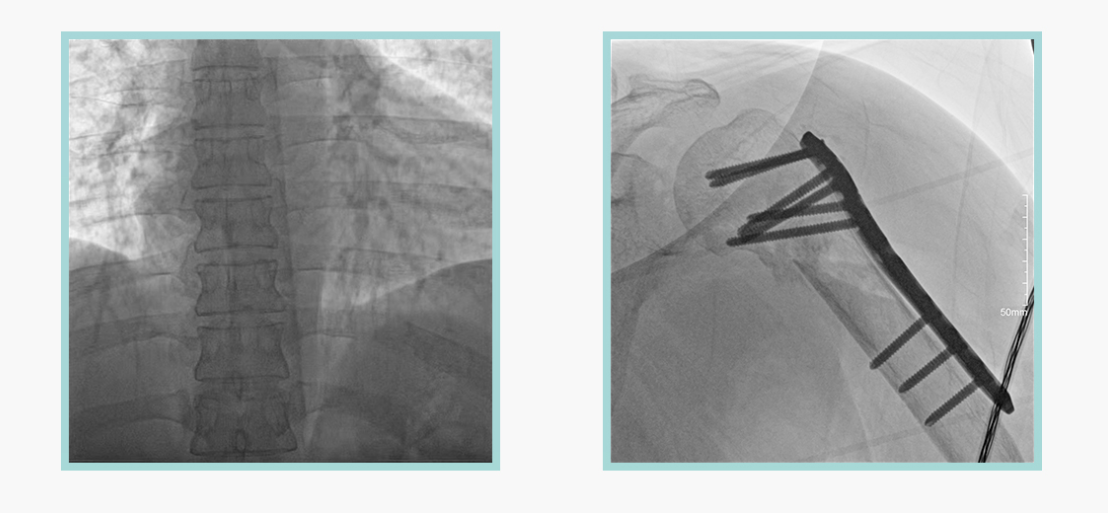

安健科技悅畫移動C臂X線攝影系統,采用了業內技術最尖端的CMOS探測器。基于性能優異的針狀CSI閃爍體涂層和高靈敏度的CMOS感光芯片,悅畫可以實現在超低X線劑量條件下實現高清晰影像成像,相較于一般的影增移動C臂和平板C臂,動態范圍更高,影像的層次感和對比度更好。

在產品的性能參數設計上,悅畫的像素可達到200萬,空間分辨率可達到3.2線對,采用16bit的影像灰度,悅畫在影像后處理上,通過SPI金字塔圖像算法,支持攝影、脈沖透視影像、連續透視等多種模式下的影像采集,動態透視影像視頻支持保存與回放。雙大屏的設計,透視影像支持三檔放大,保證臨床影像讀取的便利。

悅畫在影像的偽影處理上,也積累多項圖像處理專利技術。通過對植入物的精準識別,悅畫能夠精準祛除植入物偽影與運動偽影,保證高質量的影像輸出,無論是影像的對比度、分辨率(清晰度)相較于市面上的移動C臂產品都更勝一籌。